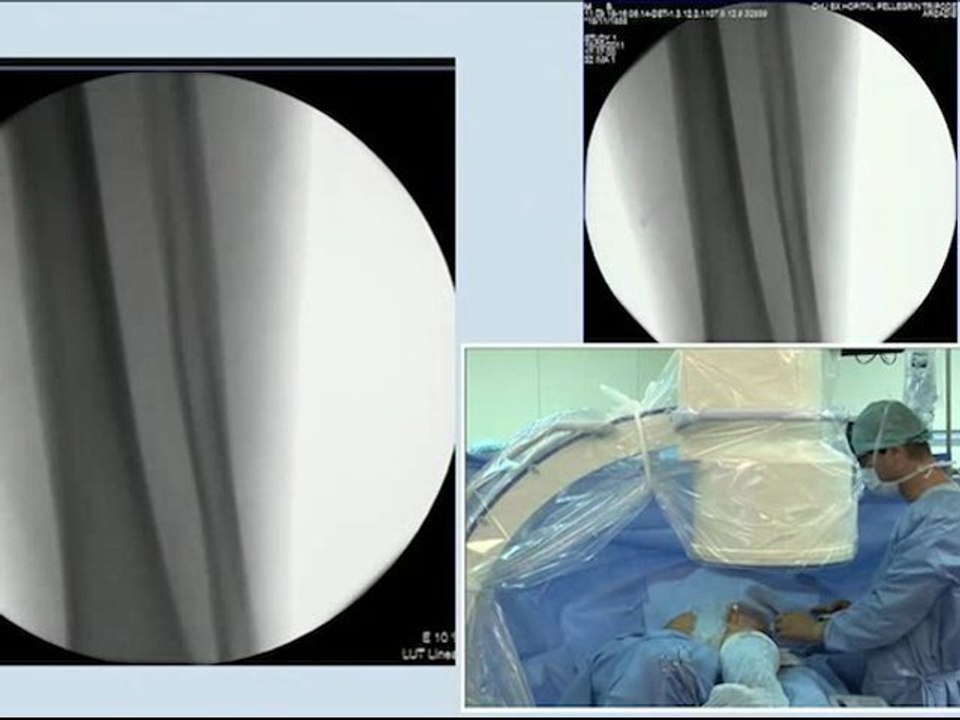

25 popliteal artery recanalisation and stenting anterior tibial artery angioplasty incathlab.com